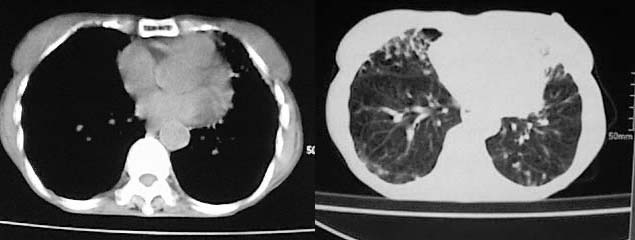

以下是引用zjzjr在2008-5-2 14:39:00的发言:[br]支持双侧继发型肺结核,左侧胸膜肥厚,慢性支气管炎伴间质纤维化.